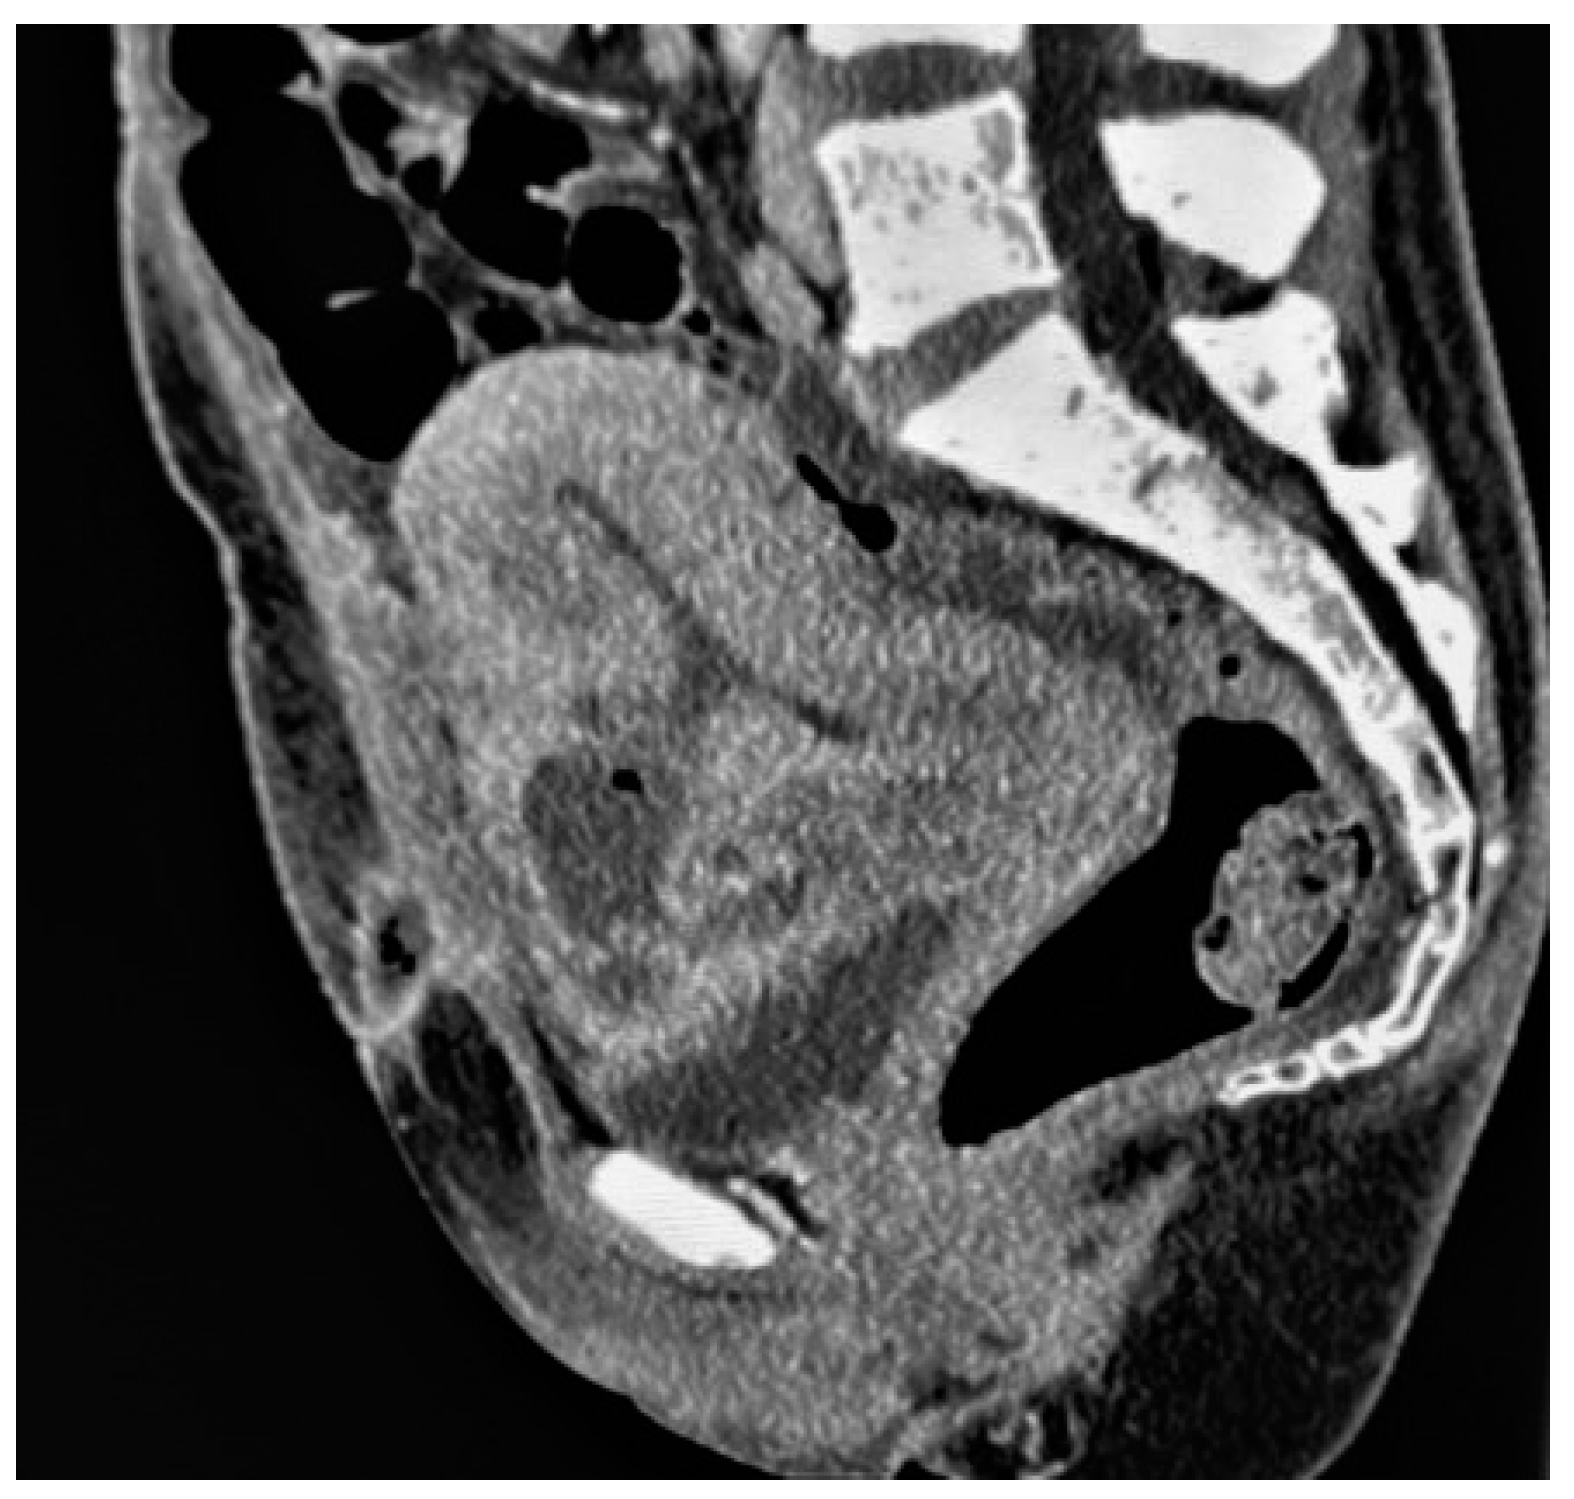

Placental/uterine bulge: deviation of the uterine serosa from the expected plane caused by abnormal bulge of placental tissue toward surrounding organs (typically toward the parametrium and bladder) can cause the uterus to take on an “hourglass” configuration due to widening of the lower uterine segment, resulting in a loss of the typical inverted pear-shape, best depicted on sagittal and/or coronal images. This finding showed a sensitivity and specificity for the diagnosis of PAS of 76.6% and 62.5% [72] (Figure 4). The specificity of this criterion increases where the bulging in the uterine contour is associated with a focal interruption of the myometrium [73].

Figure 4. A 32-year-old pregnant patient at 28 weeks of gestation with acute pelvic pain. Axial (a) and sagittal T2-weighted images (b) demonstrate a heterogeneous placenta, with abnormal placental bulging, dark intraplacental bands, and interruption of the myometrium.